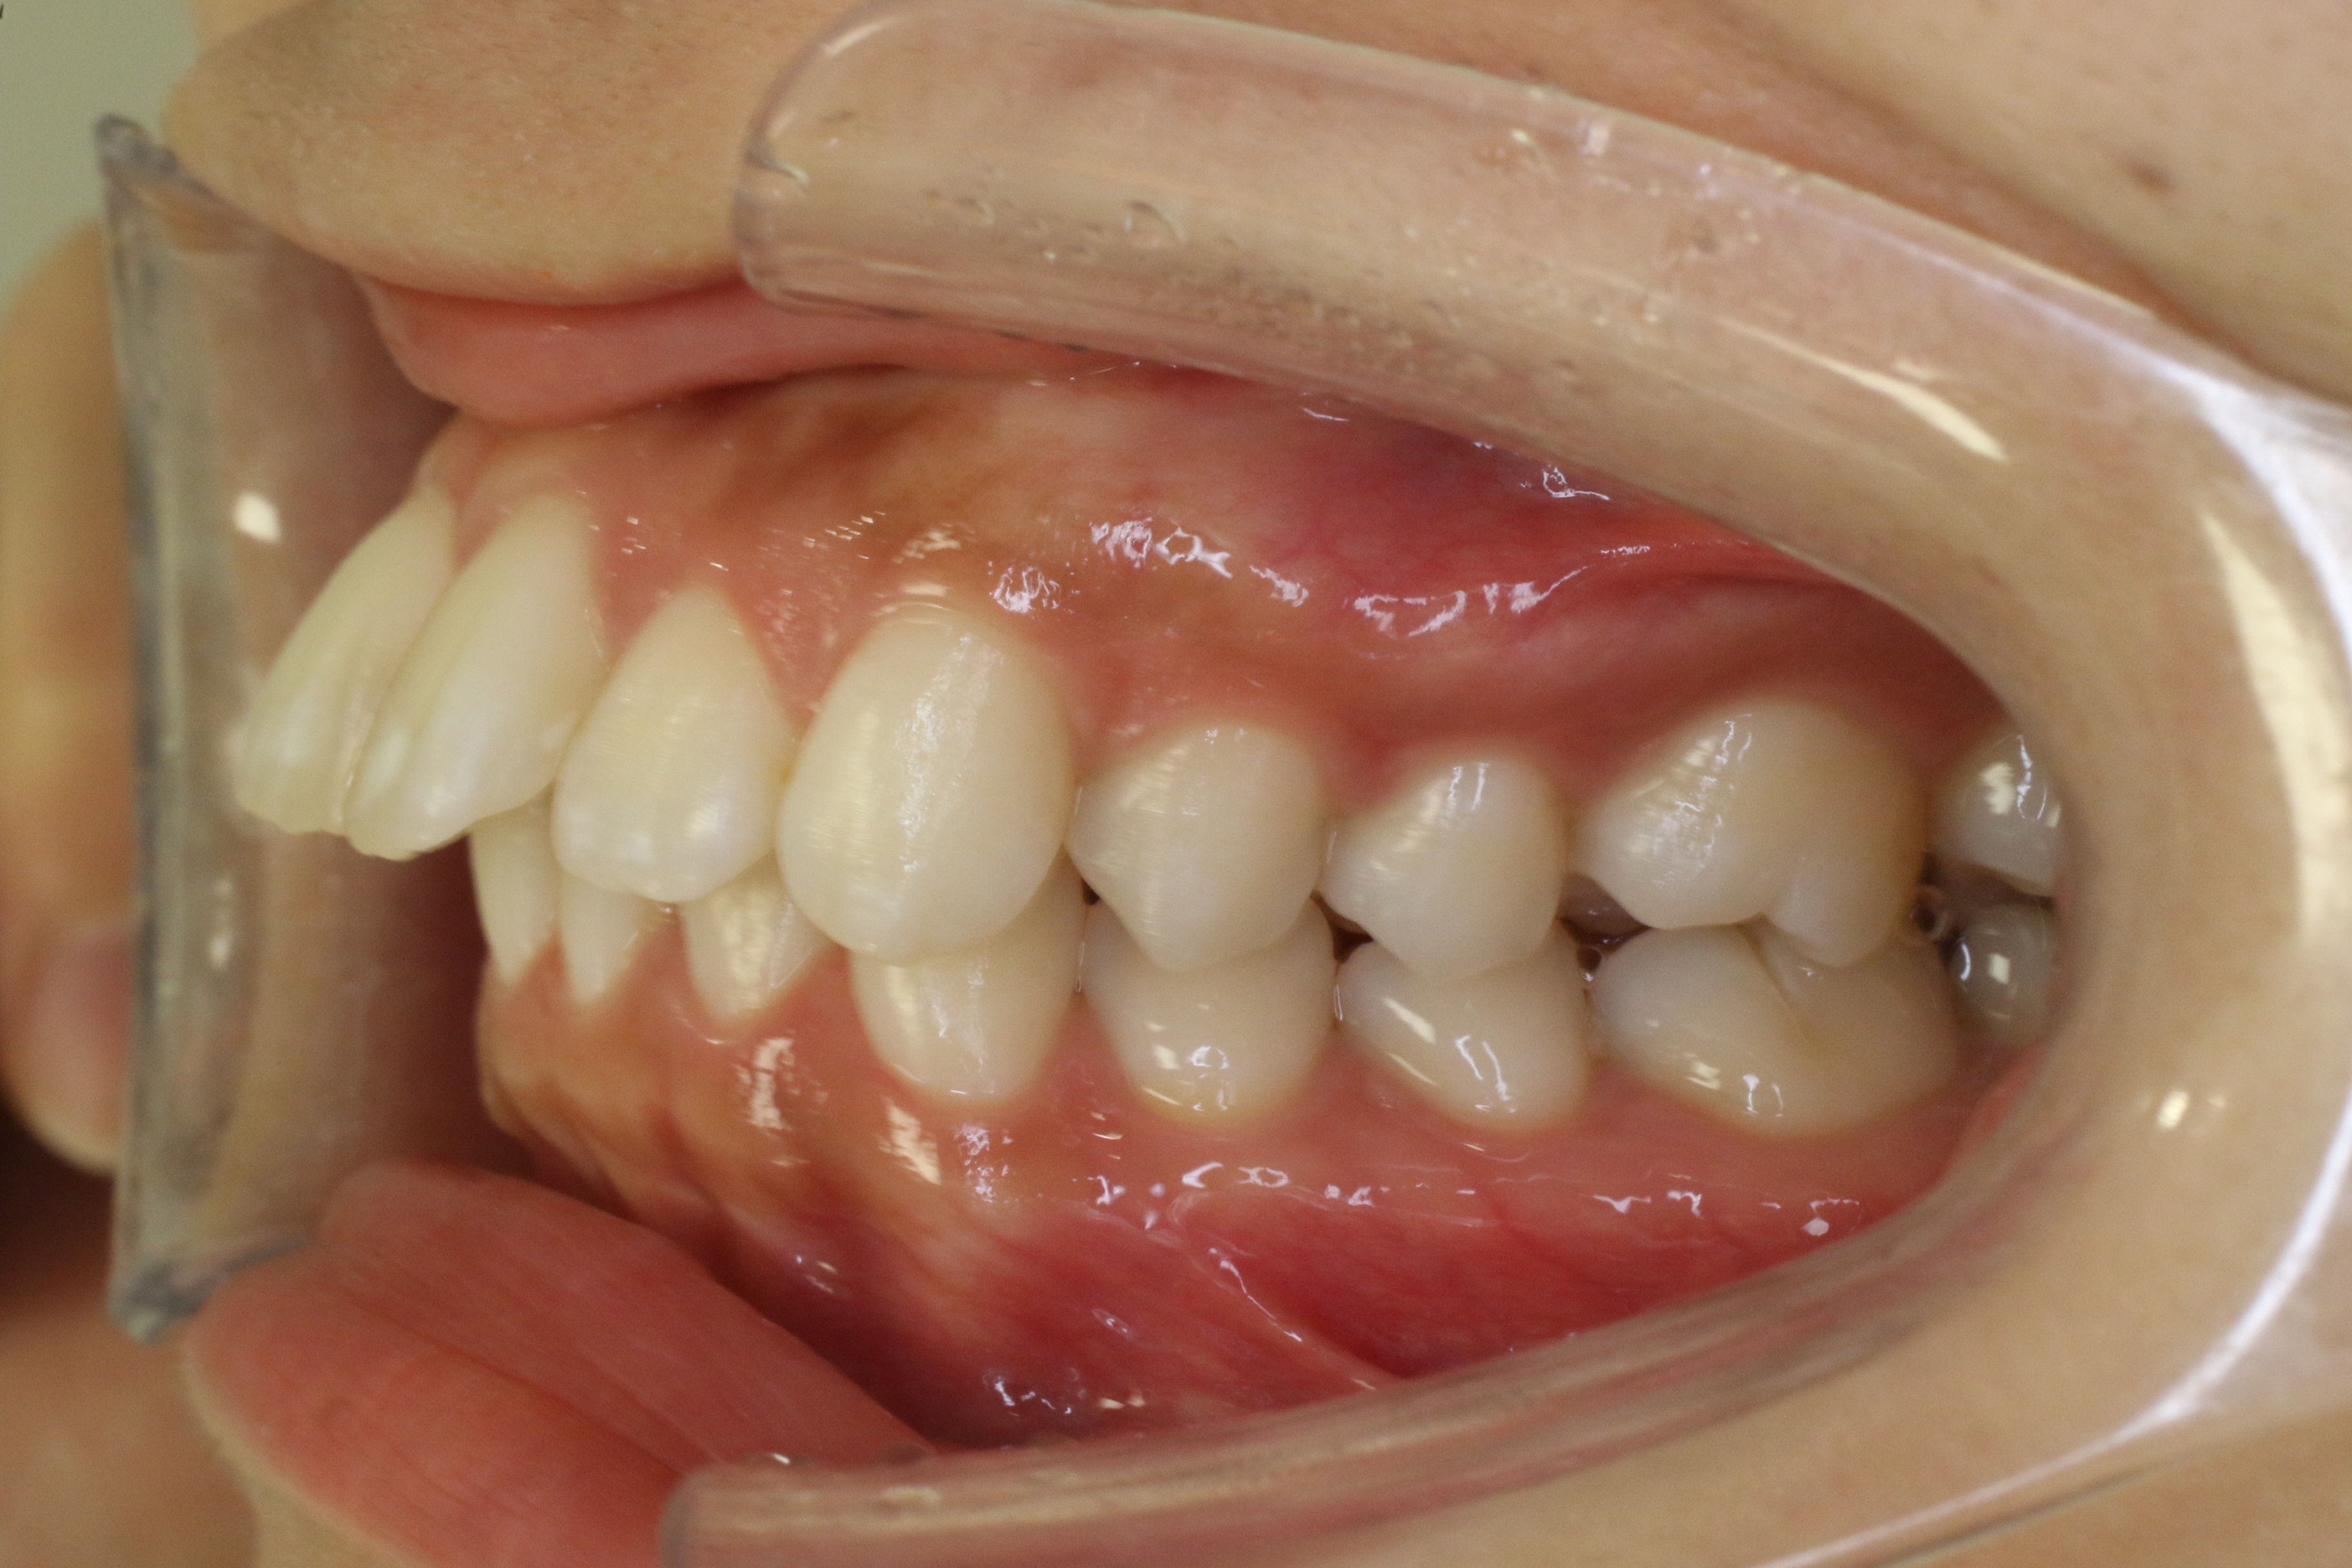

受け口を治したい

年齢層 20代

性別 女性

主訴 【主訴】受け口を治したい 【診断・症状】反対咬合、上下凸凹

治療費用 検査・診断:38,500-/ハーフリンガル矯正治療:1,287,000-(※全て税込)

治療期間 約1年半(20回)

抜歯 無(非抜歯)

矯正の装置 ハーフリンガル矯正

副作用、リスク 歯肉退縮,歯根吸収,疼痛,咬合の違和感,装置の違和感,虫歯,歯肉炎

case17_受け口_before

Before